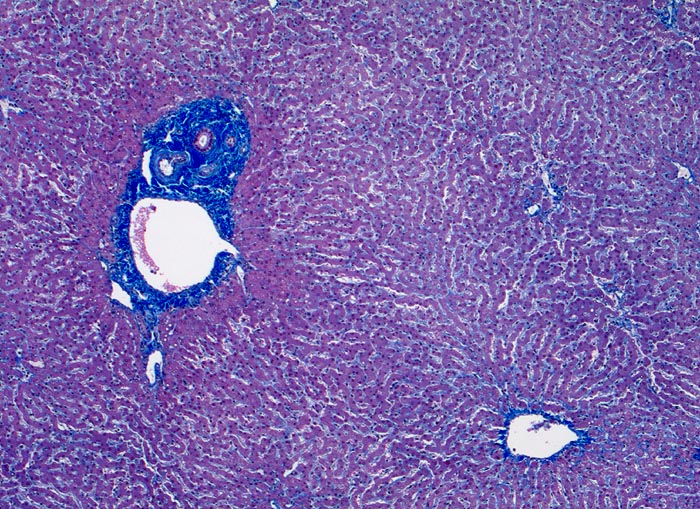

AP/ Floride alkoholische Steatohepatitis

Floride alkoholische Steatohepatitis

Leber